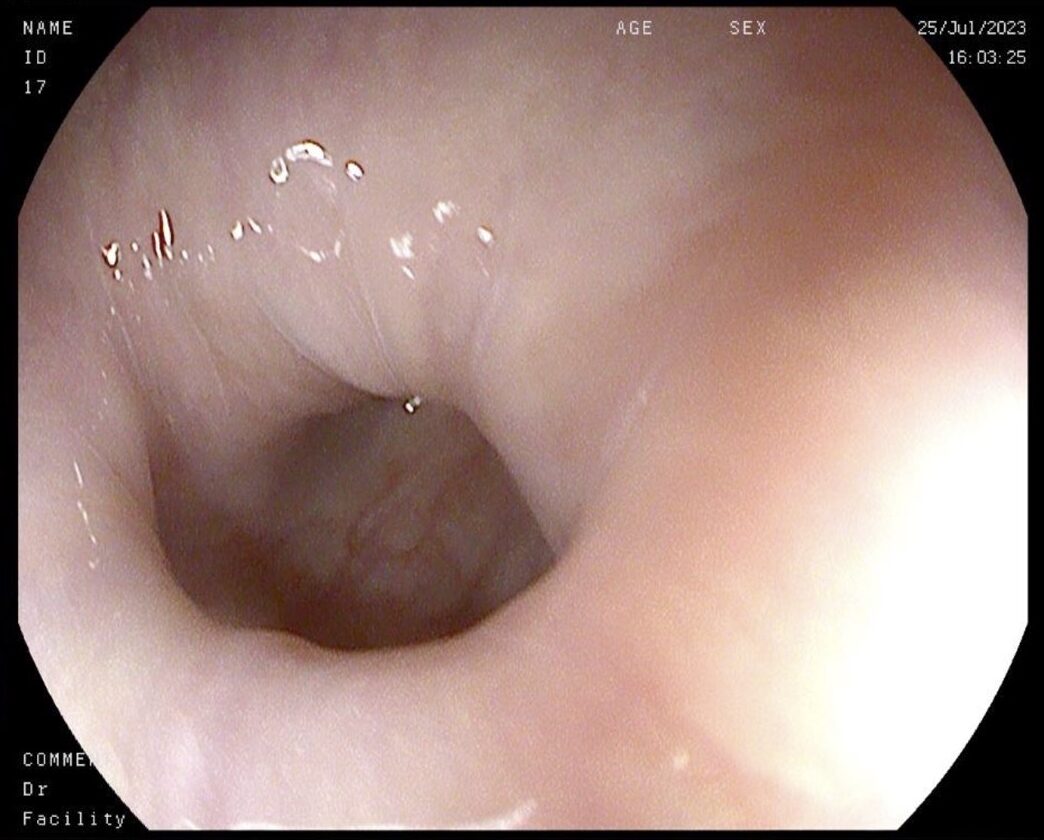

El esofagograma con contraste baritado muestra un esófago con morfología en sacacorchos marcadamente arrosariado a nivel de tercio medio y distal, con leve aumento del calibre de manera generalizada, sin evidencia de estenosis significativas (figura 2). Se observa una leve alteración de la motilidad, aunque con adecuado pase de contraste a través de la UEG.

Figura 2. Esofagograma con Bario. Esófago marcadamente arrosariado a nivel de tercio medio y distal. Adecuado paso de contraste a través de la UEG.

Por el contrario, en nuestro paciente la gastroscopia y el esofagograma realizados mostraron características típicas del espasmo esofágico distal y la manometría esofágica una presurización panesofágica similar a la observada en la acalasia tipo II.